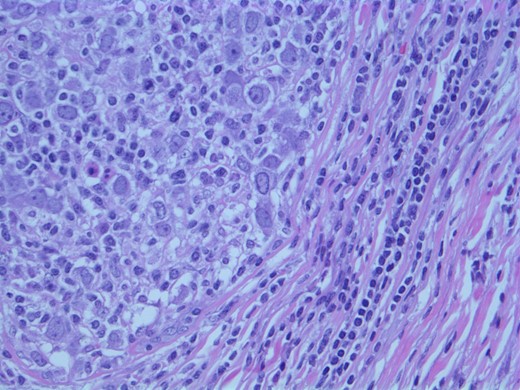

A computed tomographic (CT) scan of her chest with contrast revealed moderate right axillary lymphadenopathy and a lesion in the upper outer quadrant of the right breast measuring 1.3 × 1.2 cm (Fig. 1). A positron emission tomography (PET) scan showed a small intense focus on the right lateral breast consistent with carcinoma, significant right axillary lymphadenopathy and intense fluorodeoxyglucose hypermetabolic activity consistent with metastatic spread. Additionally, enlarged lymph nodes extending along the upper chest wall just inferior to the subclavian vessels and posterior to the pectoralis muscles were seen. A needle biopsy of the mass revealed an extensive involvement of poorly differentiated infiltrating carcinoma (Fig. 2). The tumor showed large nuclei with eosinophilic cytoplasm and prominent nucleoli consistent with apocrine differentiation (Fig. 3). There was a significant inflammatory response to the infiltrating tumor noted. No lymphovascular invasion was identified within the core biopsies. The specimen was estrogen and PR negative as well as HER-2/neu negative.

Photomicrograph: large nuclei with eosinophilic cytoplasm and prominent nucleoli consistent with apocrine differentiation.

Histologically, apocrine carcinomas display a characteristic granular eosinophilic cytoplasm, sharp boarders, round nuclei and prominent nucleoli [5]. Testing for expression of the GCDFP-15 protein on immunohistochemical staining has been used to diagnose apocrine breast carcinoma; however, decreased levels have been seen with advanced disease as well as node-positive apocrine carcinoma [6]. Detection of cancer spread can be made with chest X-ray, bone scan, CT, MRI and PET scan. After completion of these tests, one can determine the cancer's stage [7].